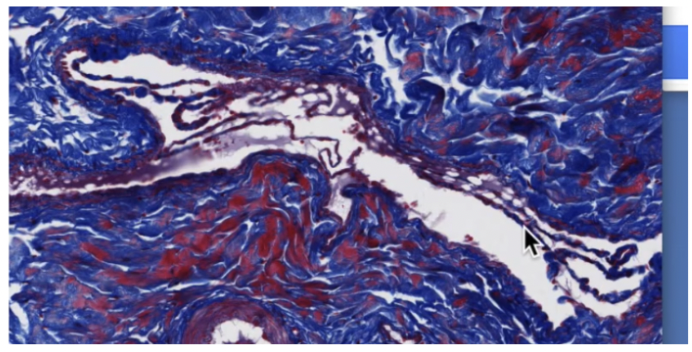

Venules are?

Venules:

Smallest veins

Postcapillary venules

Formed when capillaries join together, appear like continuous capillaries

Receive blood from capillaries

Only have tunica intima

Muscular venules

1-3 layers of smooth muscle cells in tunica media

Veins and venules often travel together